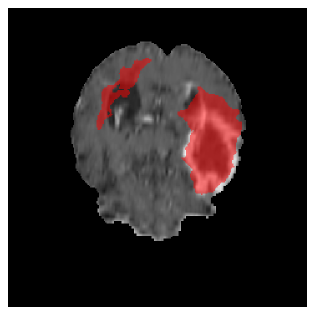

Appendix A Qualitative results

Figures 4 and 5 present the segmentation results for a patient from the BRATS dataset, visualized on a randomly selected slice. Figure 4 illustrates how tumor segmentation evolves over multiple episodes in S1 across different approaches including cumulative, naive, our approach, and the best buffer-free strategy (SI, =2). The cumulative approach, which trains on all encountered datasets together, maintains segmentation consistency across episodes but introduces significant amounts of false positives, particularly in the upper left area of the brain images. These misclassifications highlight its inability to generalize well across datasets despite access to all previous data. The naive approach, which learns sequentially without any continual learning strategy, suffers from severe catastrophic forgetting. While it initially segments well, performance deteriorates over episodes, leading to a near-complete loss of segmentation capability by the final episode. The SI (=2) approach, a regularization-based buffer-free CL strategy, performs reasonably well in early episodes but shows a significant performance decline over time. By the last episode, much of the tumor was no longer segmented, indicating difficulty in retaining prior knowledge. In contrast, our proposed approach initially produces more false positives but progressively refines its segmentation. By the final episode, it accurately retains the tumor region while minimizing misclassifications, demonstrating strong knowledge retention and adaptability across episodes. This suggests that our approach effectively mitigates catastrophic forgetting while maintaining segmentation performance over sequential learning.